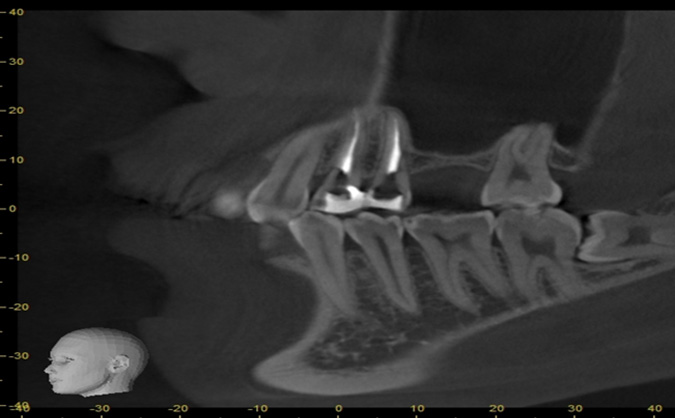

症例10

治療前

治療後

治療後のレントゲン写真

治療後の口腔内写真

主訴 噛むと痛い

治療期間 6ヶ月~8ヶ月

治療費 450,000円

治療内容 インプラント精密検査(口腔内写真/CT/模型)

抜歯 骨補填材(足りない骨を人工骨として補填)

インプラント治療

治療のリスク 骨の状況次第で抜歯と同時に人工骨填入が必要となる場合があります。

主訴

噛むと痛い

治療期間

6ヶ月~8ヶ月

治療費

450,000円

治療内容

インプラント精密検査

(口腔内写真/CT/模型)

抜歯 骨補填材

(足りない骨を人工骨として補填)

治療のリスク

骨の状況次第で抜歯と同時に人工骨填入が必要となる場合があります。

インプラント精密検査(CT撮影)

治療内容 当院ではCT撮影を行いシュミレーションを行い正確なインプラントの埋入位置の決定し手術を行っております。

当院ではCT撮影を行いシュミレーションを行い正確なインプラントの埋入位置の決定し手術を行っております。